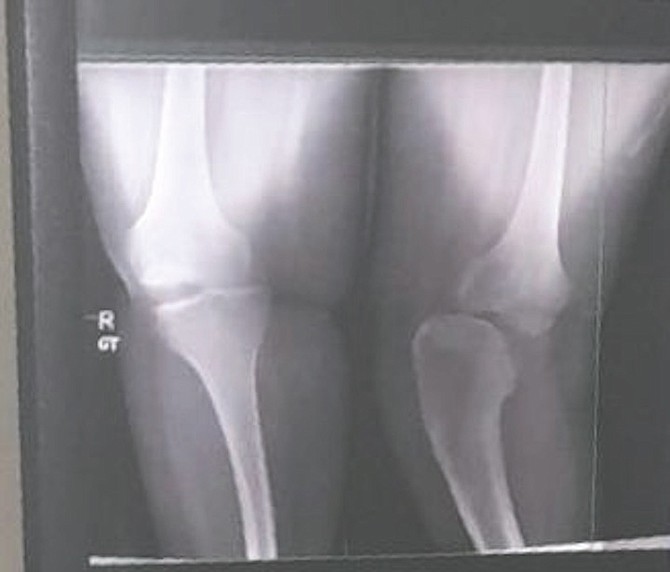

KEIRANIQUE Dorsett was born without fibular bones (as seen in the x-ray above) and other conditions that have severely impacted her life. She is hoping to raise enough funds through a GoFundMe to have surgery that would help her live a more normal life.